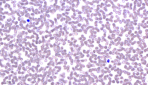

Liu’s-stain_Blood_viewcapture-3